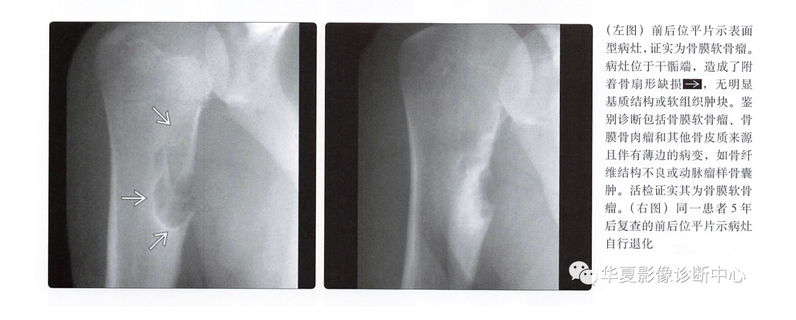

平片表现

- 骨皮质扇形凹陷

- 硬化边

- 致密性骨膜反应,尤其是在病灶近端、远端

- 病灶远端、近端骨皮质杯状改变

- 基质钙化(75%)

- 软组织肿块

鉴别诊断

骨膜软骨肉瘤

- 很少见的表面型软骨肉瘤

- 与骨膜软骨瘤发病部位相同

- 通常为低度恶性,因此可能不会出现明显侵袭性

- 几乎与骨膜软骨瘤影像表现相同

- 骨表面病灶

- 骨皮质呈扇形塌陷改变

- 基质钙化